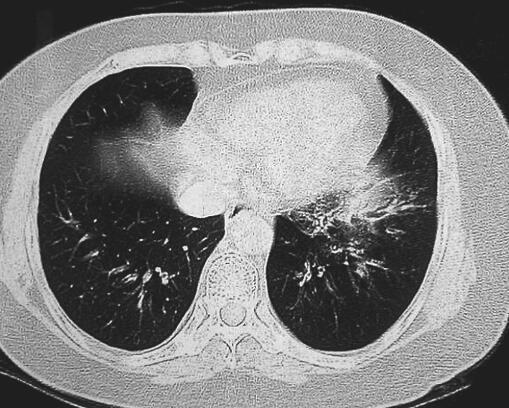

入院后查体:体温36.9℃,脉搏89次/分,呼吸频率19次/分,血压139/80mmHg。口唇无发绀,咽部充血,有滤泡增生,双侧扁桃体无明显肿大。颈软,气管居中,双肺叩诊呈清音,呼吸音低,未闻及干湿性啰音,心率89次/分,律齐,腹部平软,无压痛及反跳痛,肝脾未扪及。血常规:白细胞4.19×109/L,中性粒细胞比例0.79,嗜酸性粒细胞0.00,血红蛋白137g/L,红细胞4.83×1012/L;空腹血糖、电解质、肾功能、肝功能、血脂均未见特殊异常。肺功能示:FEV1 2.07L,占预计值的87.1%,FEV1/FVC 75%。肺弥散功能正常。入院后3次痰培养1次提示金黄色葡萄球菌阳性,2次铜绿假单胞菌阳性。胸部CT示左肺下叶基底段见条絮状密度增高模糊影,提示左肺下叶感染征象(图1)。

图1 2012年9月24日胸部CT

左肺下叶基底段见条絮状密度增高模糊影